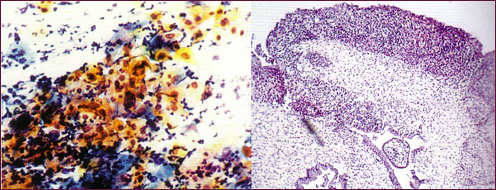

Para visualizar las paredes de la vagina y del cuello uterino, se introduce un espéculo que abre las paredes de la vagina, se limpia la mucosa con una dilución de ácido acético, se pueden utilizar diferentes colorantes como lugol y distintos tipos de luz para diferenciar la mucosa normal de la patológica. Cuando se le pone lugol a el cuello del útero y existe una lesión este no se pinta en su totalidad solo las partes sanas, de esta manera nos permita elegir la parte en la que se va a realizar una biopsia.